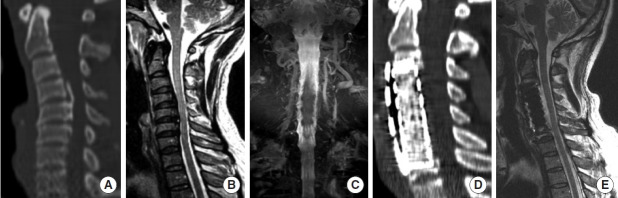

目的:分析后纵韧带骨化(OPLL)所致脊髓病和颈椎后凸患者行多节段前路截骨后路内固定后的长期临床和影像学结果。方法:接受多节段前路截骨后路内固定治疗opll性脊髓病和颈椎后凸的患者,随访时间至少为5年。分析术前、术后立即及最新随访时间点的临床结果(日本骨科协会颈椎病评分系统[C-JOA]、12项简短健康调查[SF-12]、颈部残疾指数[NDI])及影像学参数(C2-7前凸度、头部重心[CGH]-C7矢状垂直轴[SVA]、T1斜率)。结果:纳入28例患者。平均随访66.4个月。所有临床结果参数均有显著改善。C-JOA、SF-12和NDI在最新随访中均有显著改善(结论:多节段前路截骨联合后路内固定是一种安全有效的治疗opll性脊髓病伴颈椎后凸的手术选择。需要进一步的研究来调查手术后颈椎向前倾斜的情况。

Methods: Patients who underwent multilevel anterior osteotomy with posterior instrumentation for OPLL-induced myelopathy and cervical kyphosis and had a minimum of 5-year follow-up were included. Clinical outcomes (Japanese Orthopaedic Association score system for cervical myelopathy [C-JOA], 12-item Short Form health survey [SF-12], Neck Disability Index [NDI]) and radiological parameters (C2-7 lordosis, center of gravity of the head [CGH]-C7 sagittal vertical axis [SVA], T1 slope) were analyzed at the preoperative, immediate postoperative, and latest follow-up timepoints.

Results: Twenty-eight patients were included. The average follow-up period was 66.4 months. All clinical outcome parameters showed significant improvement. C-JOA, SF-12, and NDI showed significant improvement at latest follow-up (p<0.001). C2-7 lordosis increased significantly immediately postoperatively (-6.0°±10.4°) compared to preoperatively (+9.2°±9.6°), and was largely maintained at latest follow-up (-5.7°±9.4°). T1 slope significantly increased between the immediate postoperative timepoint (21.9°±7.7°) and latest follow-up (24.2°±9.5°) (p=0.046). CGH-C7 SVA significantly increased between the immediate postoperative timepoint (22.7±14.8 mm) and latest follow-up (32.2±22.6 mm) (p=0.046).